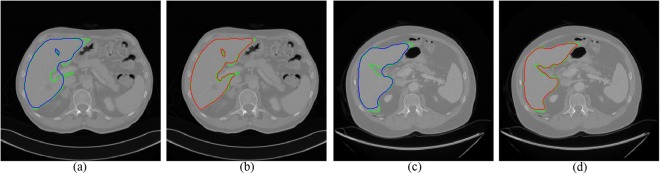

To test on the 3Dircadb1 dataset, we compared the proposed method with interactive graph cut using image intensity only. Figure 6 shows two slices of segmentation results by two methods. The green curves are the ground truth of liver. The blue curves in Fig. 6a,c are the segmentation results using original graph cut. It can be found that some vessels are included. With the help of multi-dimensional graph cut, these vessels can be excluded, as shown in Fig. 6b,d with red curves. The comparison of Dice measure using two methods is shown in Fig. 7. Compared to original graph cut, the mean of Dice measure increases significantly from 0.88 to 0.94.

Figure 6.

Two examples of segmentation results by different methods. The ground truth is shown in green curves. (a) and (c) Segmentation using original graph cut (blue curves). (b) and (d) Segmentation using the proposed method (red curves).